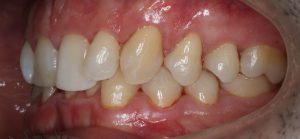

Maloclusión

Se caracteriza por una alineación incorrecta de los dientes, donde los dientes superiores e inferiores están en una relación normal, pero hay una falta de espacio que provoca que los dientes se solapen o estén apiñados.

Este problema puede generar dificultad para mantener una correcta higiene dental y afectar la estética de la sonrisa